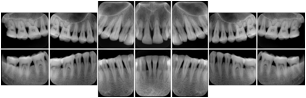

- OO-1. Intra-oral Full Mouth Series Structured Display